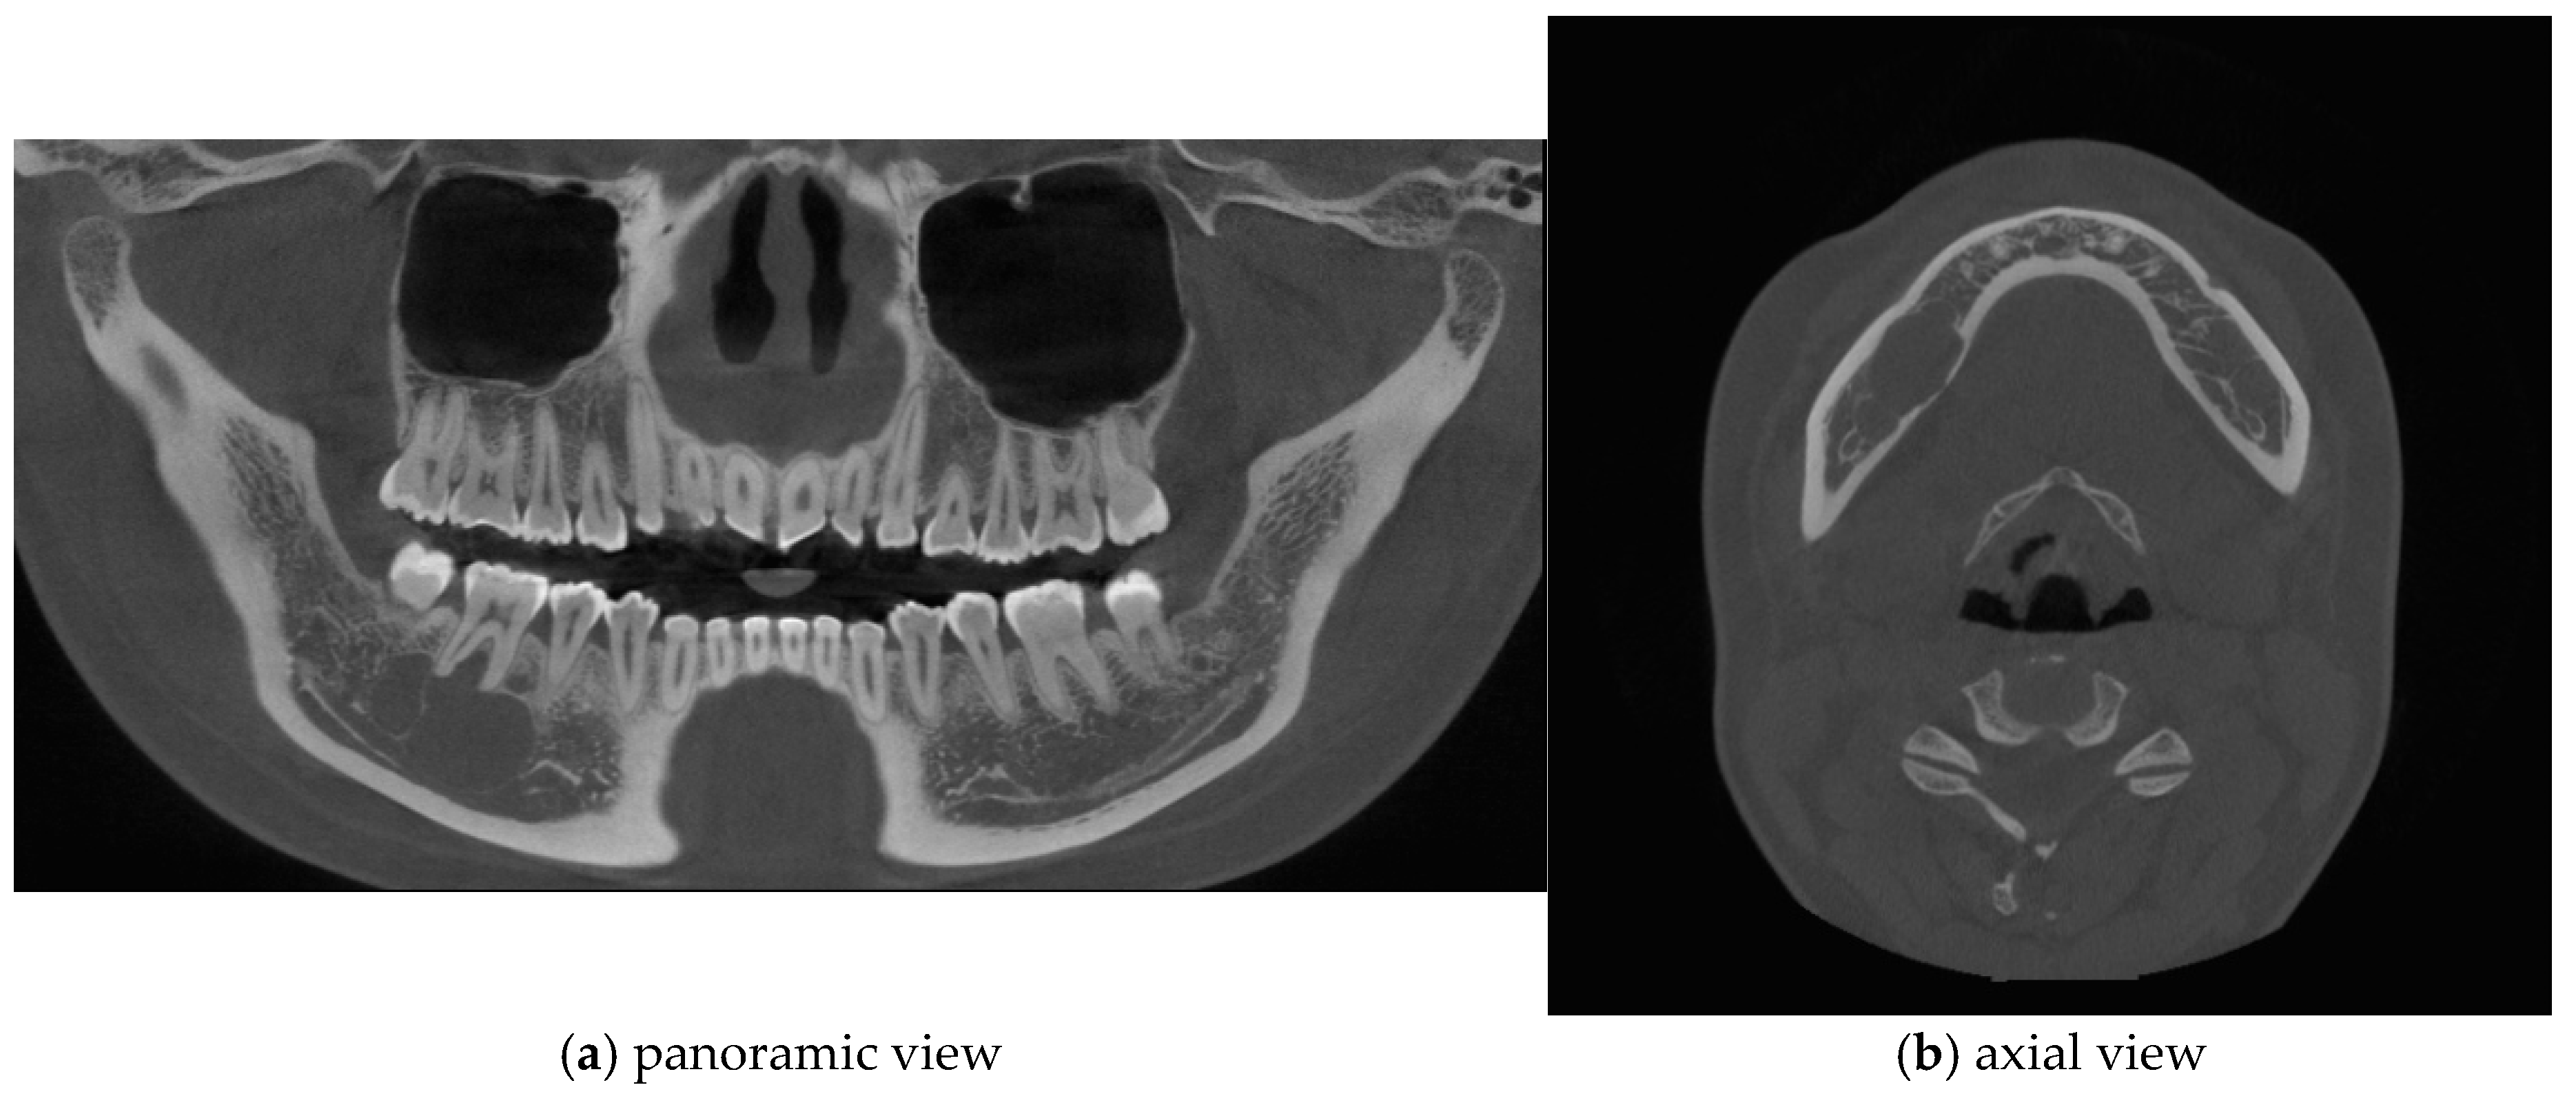

Postoperative panoramic radiographs and CBCT imaging were obtained to evaluate the error compared to the preoperative plan. (Figure 11) The evaluation was performed using Materialize 3-matic software. After aligning the preoperative plan STL model and the postoperative STL model, the average value was obtained through analysis of the difference between the two models. the average discrepancy was 0.79 mm. During the 6-month follow-up period after surgery, occlusion and mouth opening were stable.

Figure 11.

Postoperative panoramic radiograph and cone-beam CT. A high level of precision was achieved in the reconstruction.

One of the primary benefits observed in this case was the high level of precision achieved in the reconstruction. Postoperative panoramic radiographs and cone-beam CT scans showed that the actual reconstruction closely matched the virtual surgical plan (Figure 12A,C). When comparing the overall preoperative and postoperative results, the average discrepancy was 0.90 mm. This level of accuracy is consistent with findings in the literature, where studies have reported average differences between virtual plans and postoperative results ranging from 0.9 mm to 3.0 mm [9,19,20,21,22,23,24,25,26,27].